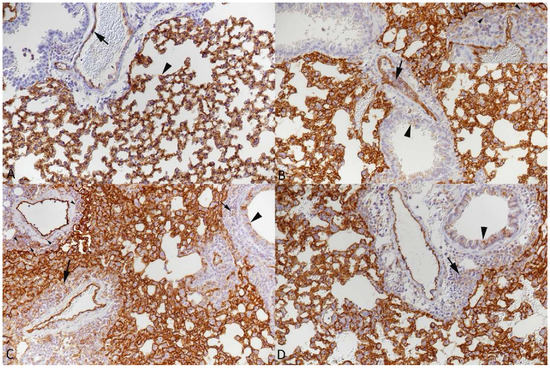

3.2. Respiratory Virus Infections, with Variable Degree of Alveolar Damage, and with or without Damage to Respiratory Epithelium, Elicit a Stereotypic Vascular Response

3.4. The Vascular Response after Respiratory Virus Infections Is Associated with Increased Expression of Adhesion Molecules in the Lungs